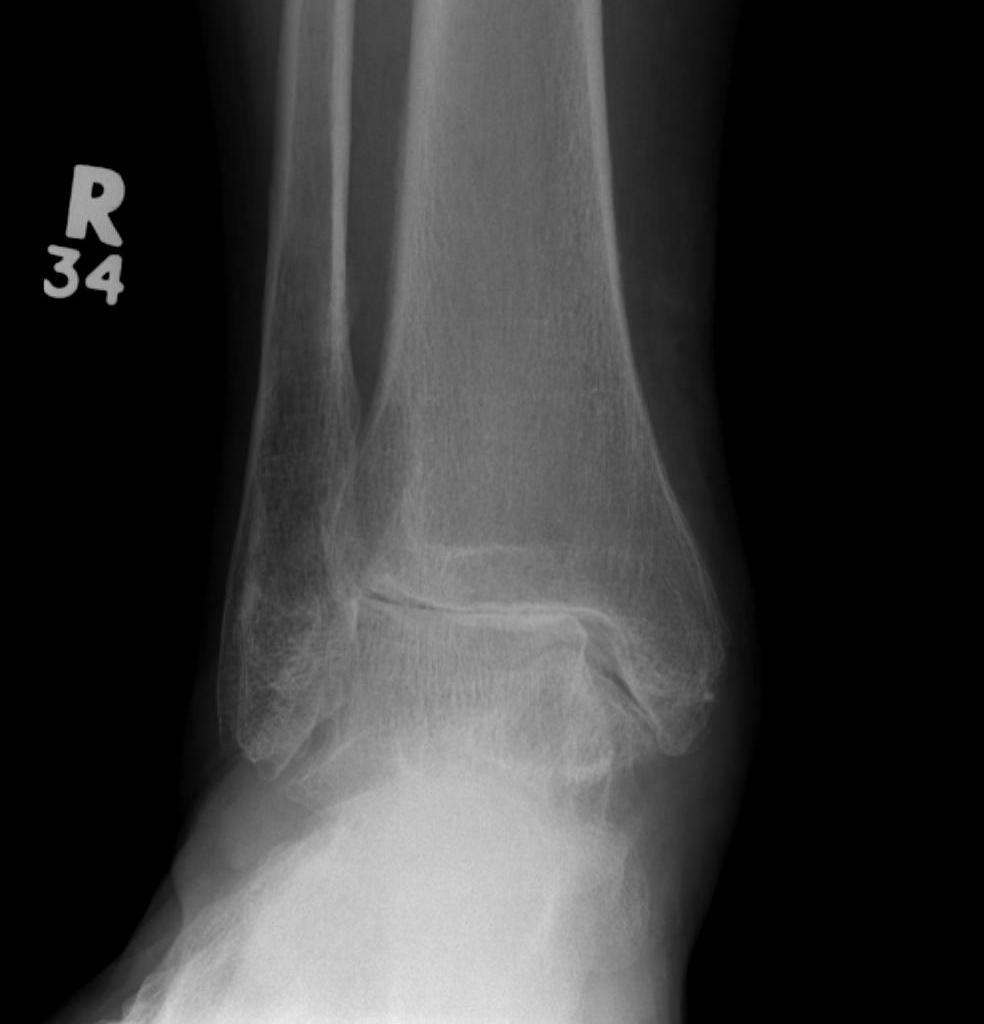

Ankle Arthroplasty

History